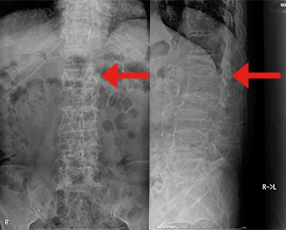

椎体骨折後骨癒合が得られない状態が継続して下肢の脱力が生じています。